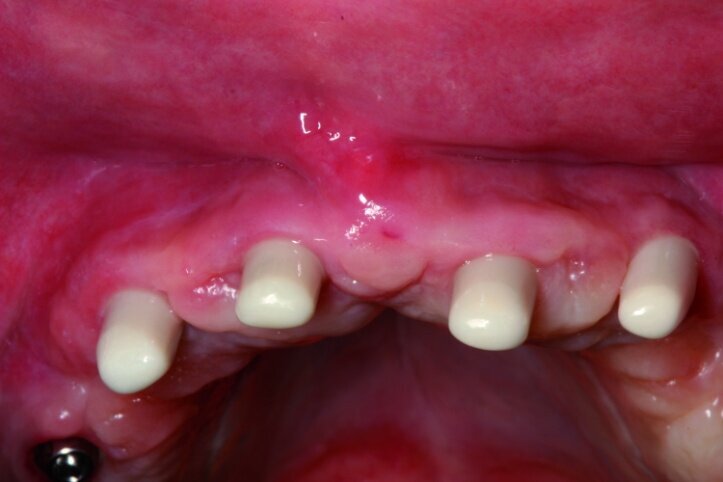

Each treatment should start with a well-prepared plan. For most patients appearance after treatment will always be very important that is why an intraoral analysis must be made in order to assess the static structure of the mouth, as well as an analysis of the lips’ dynamics along with teeth exposure during speaking and smiling (Figs. 1 & 2).

We analysed the aesthetic aspects in a way that enables us to reach an optimal balance between white (teeth) and pink (gums) aesthetics. Of course, in toothless patients, one should take note of the fact that teeth setup as well as reconstruction of atrophied tissues will constitute a support for the lips. Such an analysis may be made on the basis of a restoration that the patient uses. In this case, first sanitation of the maxilla had to be performed, next a temporary acrylic prosthesis was made.